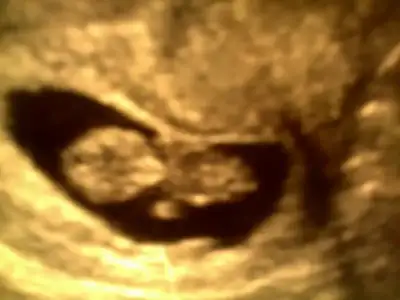

$image.webp İkiz minnoşlarım teyzeleri:)

buda bizim en son resmimiz teyzeleri.10+2 :nazar::nazar::nazar::nazar:

yaa hamile olan arkadaşlar siz de ultrason fotoğrafını koysanızda topiğimiz yumurcaklarla şenlense biraz:8::28: